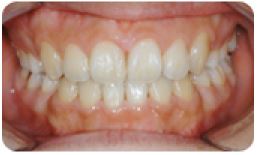

치아교정 레진브라켓 전후사례 | 2020.03.06 |